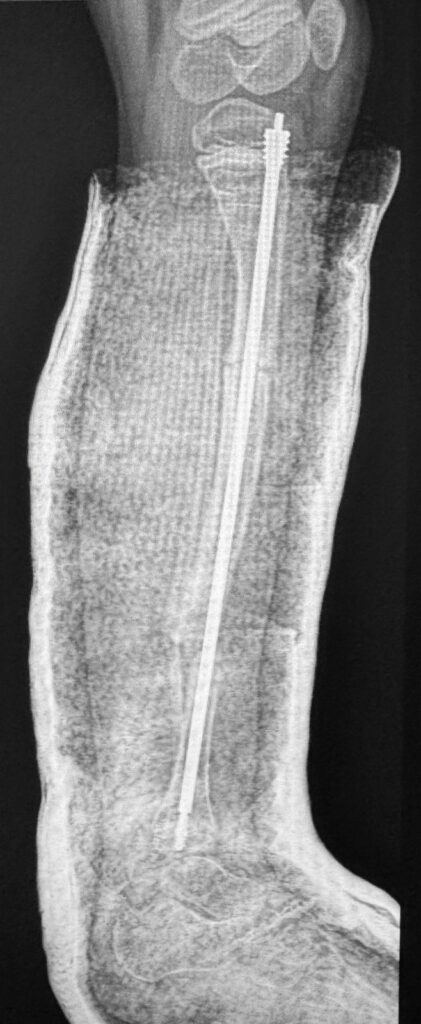

O paciente, que sofria de múltiplas fraturas recorrentes e apresentava uma grave deformidade na perna esquerda, foi tratado com a implantação de uma haste intramedular telescopada Fassier-Duval. Esse dispositivo, que se ajusta ao crescimento do osso, oferece suporte e estabilidade, prevenindo fraturas à medida que a criança cresce.

Apesar da complexidade do procedimento, devido à fragilidade óssea característica da doença, a cirurgia foi um sucesso. O pós-operatório foi tranquilo, com alta no dia seguinte e imobilização gessada simples. A criança iniciará fisioterapia nas próximas semanas.